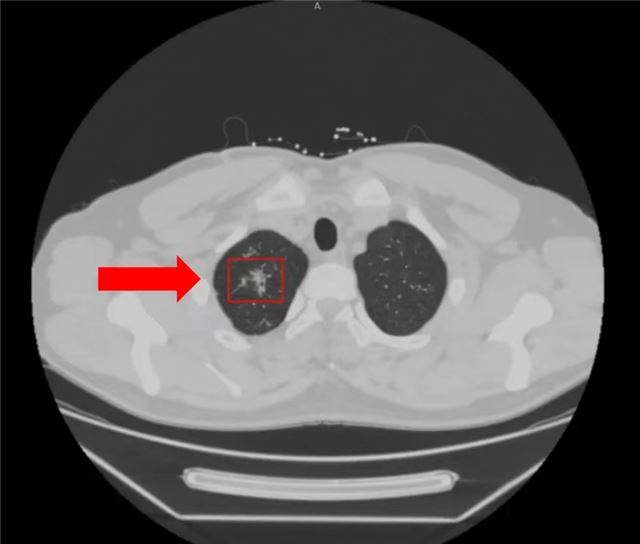

一名年轻的男性患者,因“右侧胸背部疼痛3个月”就诊于我院呼吸与危重症医学科,胸部CT检查提示右肺上叶散在斑点、条索、钙化灶,慢性炎性病变可能。

根据胸部CT结果,初步考虑该患者为肺结核的可能。科室进行了电子气管镜肺泡灌洗,完善了肺泡灌洗液结核菌鉴定及耐药基因检测(Xpert MTB/RIF)等结核相关检查。